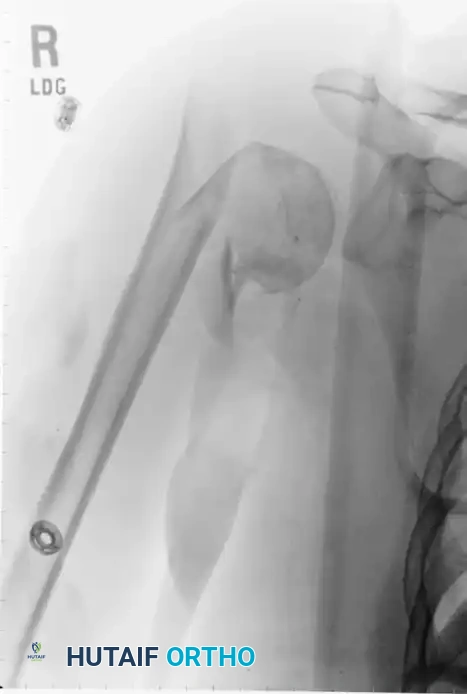

التثبيت باستخدام المسمار النخاعي

يوفر المسمار النخاعي ثباتاً ميكانيكياً قوياً جداً، حيث يتم إدخاله داخل التجويف النخاعي لعظمة العضد. يُعتبر هذا الخيار مثالياً للكسور التي تمتد إلى منتصف ذراع المريض.

من أهم مميزات المسمار النخاعي أنه يوفر تثبيتاً ممتازاً حتى في العظام الضعيفة، ولا يحتاج لشق جراحي كبير. التصميمات الحديثة لهذه المسامير تحتوي على براغي قفل متعددة الزوايا تمنع العظام من الانزلاق. ومع ذلك، يتطلب إدخال المسمار شق جزء صغير من وتر العضلة فوق الشوكية، مما قد يسبب بعض الألم المؤقت في الكتف بعد العملية.

إليك بعض الصور الإشعاعية والرسوم التوضيحية الإضافية التي توضح أشكال التثبيت الجراحي المختلفة لكسور أعلى عظمة العضد